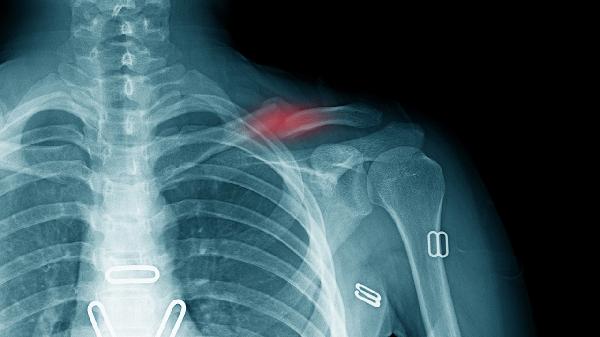

锁骨骨折恢复期需建立均衡膳食模式,除上述重点营养素外,还应保证新鲜蔬果摄入以提供抗氧化物质。避免高盐、高糖及含磷碳酸饮料影响钙代谢,戒烟限酒以防血管收缩阻碍愈合。餐后适当活动促进消化吸收,但需避免患侧负重。定期复查X线观察骨痂生长情况,若出现愈合延迟需在医生指导下调整营养方案。睡眠时保持患肢功能位,配合医嘱进行渐进式康复训练,营养与运动结合可显著提升恢复效果。